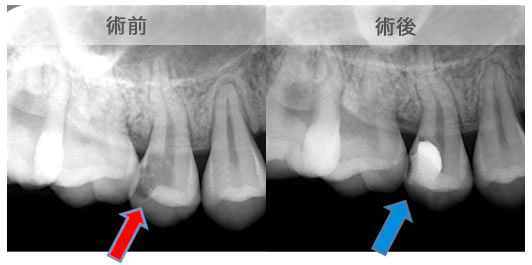

原因は赤の矢印が指す、根の周りの病巣でした。

治療後は青い矢印が指す場所には、黒い病巣が消失しています。

| 治療説明 | 自覚症状で歯が浮いた感じがしていました。上顎大臼歯・頬側根の根尖部にX線透過像の病巣があります。根充剤を除去・拡大清掃・根管充填を行いました。根尖から根充剤がはみ出ていますが、根尖部のX線透過像は見られなくなりました。そこ後、自覚症状もなくなりました。 |